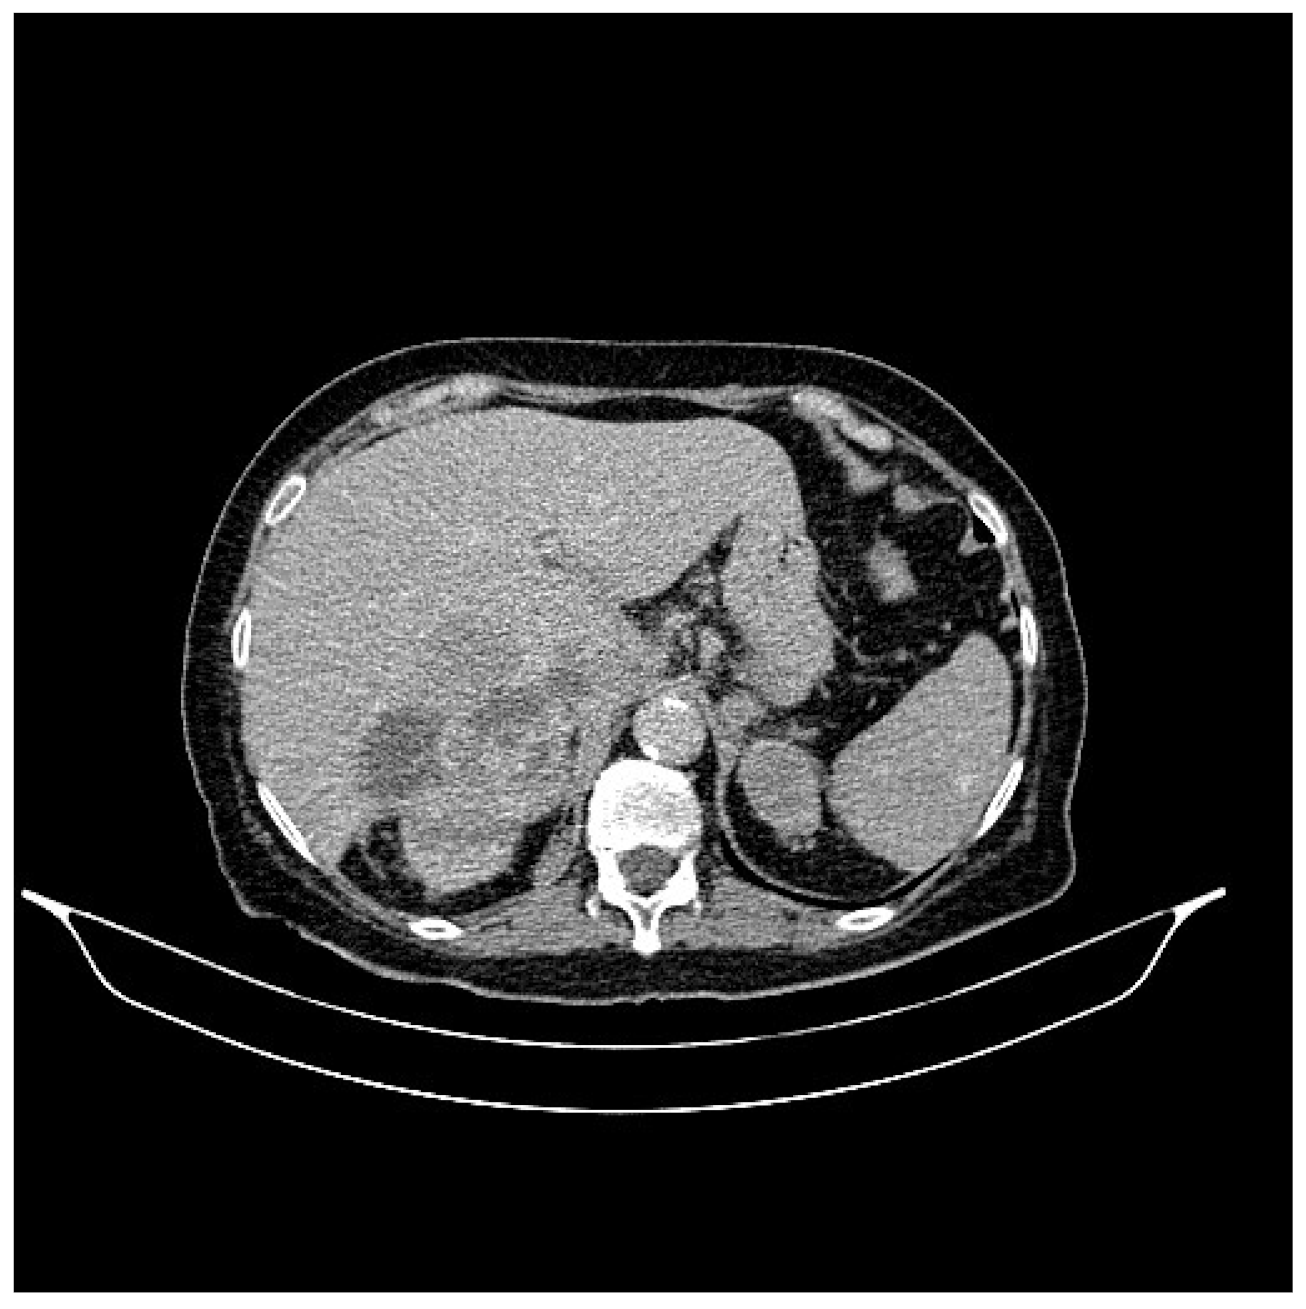

2. Case Presentation